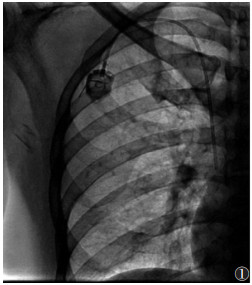

1.2 仪器与方法采用巴德5F植入式静脉输液港、穿刺套件、心电监护仪、蝶翼针。由2位具有5~10年植入经验的医师与1位护士在DSA引导下采用2种不同的穿刺入路植入输液港,术中行X线检查确保导管位置并判断有无血气胸等并发症。①锁骨下静脉入路:于锁骨下约1 cm、中外1/3交界处穿刺,在导丝引导下引入输液港,将导管末端置于上腔静脉和右心房交界处(约T6~T7椎体水平),经DSA确认后建立囊袋(锁骨下窝处)以放置港体、打通皮下隧道,连接固定港体与导管(图 1)。②颈内静脉入路:于颈内动脉偏外约0.5 cm、斜角肌三角顶点处穿刺,在导丝引导下引入导管(导管末端位置同上);建立囊袋、打通皮下隧道,连接导管与港体,注意翻转导管经皮下隧道下行至锁骨下窝处(港体埋植处)(图 2)。操作时若误入动脉,须立即停止并加压止血10 min;若出现气胸须暂停手术,并观察5~10 min,若大量气胸须行胸腔穿刺引流。

| 图 1 经锁骨下静脉穿刺入路植入输液港 |